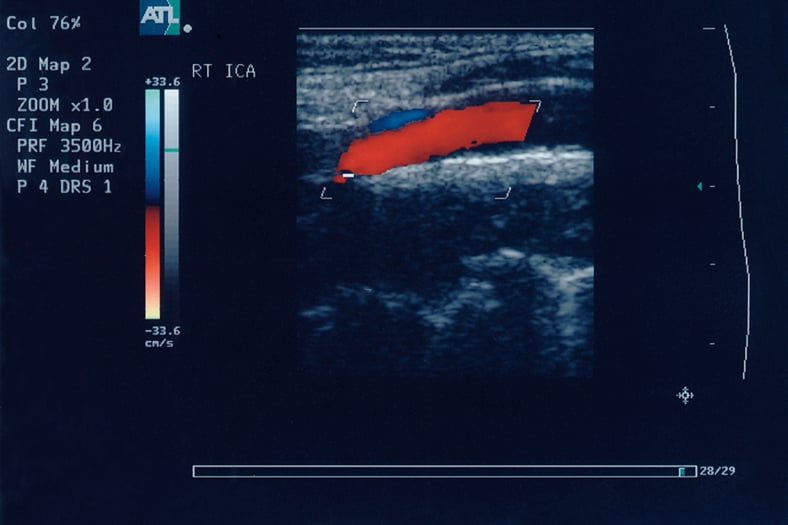

Sonography also doesn’t use medical radiation. It uses sound waves to produce an image. A transducer sends high-frequency sound waves to the area being imaged. As those sound waves bounce off organs and tissues, they send back an echo. Computer equipment converts those echoes into visual data.

Sonograph image / Image © ASRT

Sonograph image

Image © ASRT